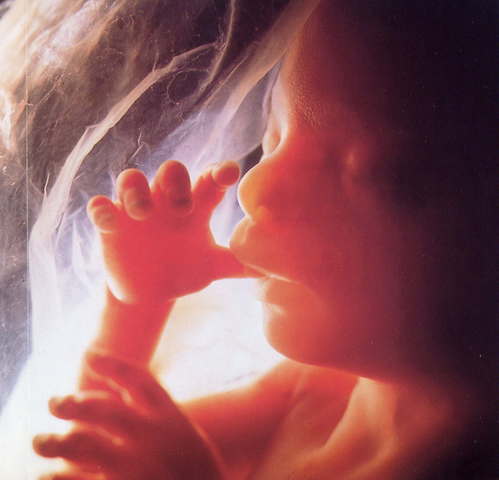

• physical development

physical development

This is where the physical appearance of the fetus begins to form. the head begins to form quickly followed by the eyes, nose, ears, and mouth.The cardiovascular system is where the activity begins as the blood vessel that will become the heart start to pulse.buds that will form the arms and legs will appear. this domain is physical